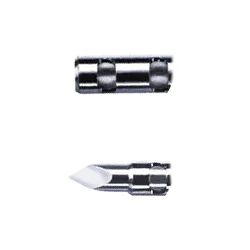

CYTO-CUT

Cytocut® je jednorázová jehla typu Chiba, navržená pro cyto-histologickou aspiraci. Díky perfektně spojeným dílům zabraňuje extrakci cizích tkání během zavádění. Pro usnadnění práce je vybavena centimetrovými značkami, posuvnou zarážkou a echogenním značkovačem, který zajišťuje vynikající viditelnost pod ultrazvukem. Co oceníte na jehle Cytocut® Přesný odběr vzorků Vylepšená viditelnost Snadná kontrola hloubky Univerzální připojení Bezpečné a spolehlivé